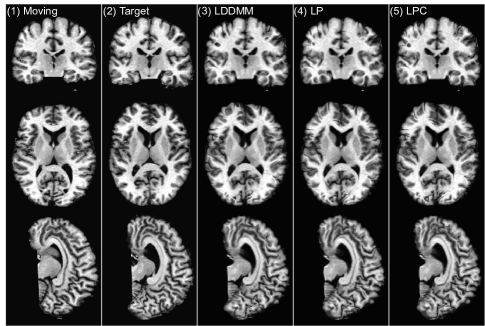

In this experiment, we use a sliding window stride of 14 for both the prediction network and the correction network during evaluation. We mainly compare the following three LDDMM-based -methods: (i) the numerical LDDMM optimization approach (LO) as implemented in PyCA, which acts as an upper bound on the performance of our prediction methods; and two flavors of Quicksilver: (ii) only the prediction network (LP) and (iii) the prediction+correction network (LPC). Example registration cases are shown in Fig. 9.

LO is the algorithm that our predictive registration approaches (LP and LPC) are based on. Hence, LP and LPC are not expected to show improved performance with respect to LO. However, similar performance for LP and LPC would indicate high quality predictions. Indeed, Table 3 shows that our prediction+correction approach (LPC) performs similar (with respect to the other registration methods) to LO. A slight performance drop with respect to LO can be observed for LPC and a slightly bigger performance drop for LP, which only uses the prediction model, but no correction model.

To assess statistical equivalence of the top performing registration algorithms we performed paired two one-sided tests (paired TOST) [71] with a relative threshold difference of 2%. In other words, our null-hypothesis is that methods show a relative difference of larger than 2%. Rejection of this null-hypothesis at a significance level of α=0.05/204𝛼0.05204\alpha=0.05/204 then indicates evidence for statistical equivalence. Table 4 shows the paired TOST results. For a relative threshold difference of 2% LPC can be considered statistically equivalent to LO for all four datasets and to many of the other top methods (e.g., LPC vs. SyN on MGH10 and IBSR18).

Overall, these statistical tests confirm that our prediction models, in particular LPC, are highly competitive registration algorithms. Computational cost, however, is very small. This is discussed in detail in Sec. 3.4.

3.2.3 Choosing the correct “correction step”

As shown in Sec. 3.2.2, LPP, LPC2 and LPC3 all result in label overlapping scores which are similar to the label overlapping scores obtained via LPC. This raises the question which method should be preferred for the correction step. Note that among these methods, only LPC is specifically trained to match the LDDMM optimization results and in particular to predict corrections to the initial momentum obtained by the prediction model (LP) in the tangent space of the moving image. In contrast, LPP, LPC2 and LPC3 lack this theoretical motivation. Hence, it is unclear for these methods what the overall optimization goal is. To show what this means in practice, we computed the determinant of the Jacobian of the deformation maps (Φ1superscriptΦ1\Phi^{-1}) for all voxels for all four registration cases of [33] inside the brain mask and calculated the histogram of the computed values. Our goal is to check the similarity (in distribution) between deformations generated by the prediction models (LP, LPC, LPP, LPC2, LPC3) in comparison to the results obtained via numerical LDDMM optimization (LO).